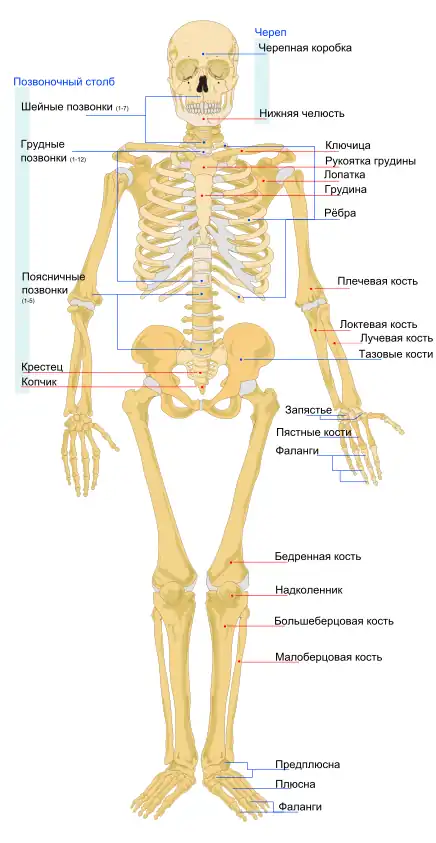

Надколенник (коленная чашечка) — самая крупная сесамовидная кость скелета человека. Располагается она в толще сухожилия четырёхглавой мышцы бедра, хорошо прощупывается через кожу, при разогнутом колене легко смещается в стороны, а также вверх и вниз. Верхний край надколенника скруглён и именуется основанием надколенника. Нижний край немного вытянут и образует верхушку надколенника. Передняя поверхность кости шероховата. Задняя суставная поверхность при помощи вертикально расположенного гребешка разделяется на две неравные части: меньшую — медиальную и большую — латеральную. У человека центр окостенения появляется в хрящевом надколеннике между 3 и 6 годами[1].

Основная функция коленной чашечки — защита от боковых смещений суставных поверхностей бедренной и большой берцовой кости, образующих коленный сустав. При сгибании и разгибании ноги коленная чашечка, расположенная внутри мощного сухожилия, смещается вверх и вниз по желобкам указанных выше костей, не давая им смещаться в стороны благодаря выступу на своей нижней (задней) поверхности. Кроме этого, по бокам коленного сустава имеются мощные крестовидные связки, которые обеспечивают дополнительную прочность сустава.